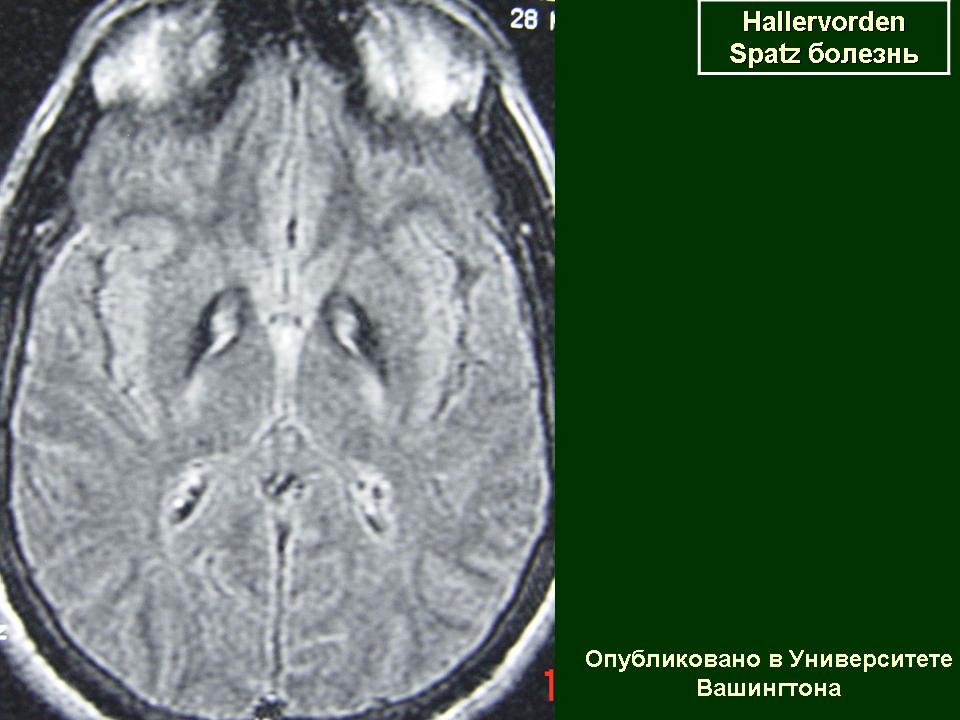

ГМ. Галлервордена - Шпатца болезнь. +

Галлервордена - Шпатца болезнь

Болезнь Галлервордена - Шпатца - наследственное заболевание экстрапирамидной системы, связанная с нарушением обмена железа и липидов и повреждением бледного шара и черной субстанции. Тип наследования аутосомно-рецессивный. При патоморфологическом исследовании характерным признаком является гиперпигментация бледного шара и черной субстанции. Обнаруживается пигментация коры полушарий большого мозга и таламуса. Пигмент находится внутри невронов и глиальных клеток, расположенных около сосудов; содержит железо (вместе с тем каких-либо нарушений обмена железа в организме не обнаружено). Наблюдаются утолщение и фрагментация аксонцилиндров в пораженных областях. Постепенно наступает дегенерация невронов коры полушарий большого мозга и мозжечка. Характеризуются нарастающей экстрапирамидной ригидностью, гиперкинезами (атетоз, торсионная дистония), затем развивается акинетико-ригидный синдром, пирамидная микросимптоматика, снижение интеллекта. Течение медленно прогрессирующее на протяжении 10 - 20 лет.

"Глаз тигра"-наглядно и красиво.

Вы правы. Выставил еще более нагладные исллюстрации.